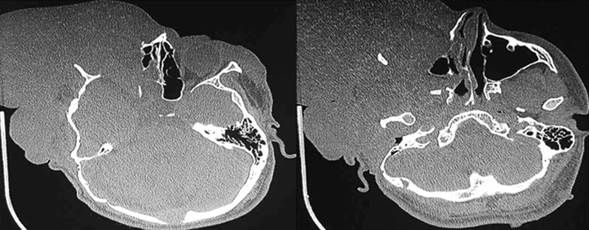

Al examen, se destaca una neurofibromatosis plexiforme orbitotemporal a derecha de gran tamaño que desplaza las estructuras de la línea media, con proptosis, blefaroptosis y ceguera del ojo derecho (figura 1). A la palpación no presenta pulsaciones ni frémito. Además, presenta nódulos de Lisch, manchas color café con leche en el cuerpo y neurofibromas subcutáneos pequeños en el tronco. En la tomografía computada se evidencia agrandamiento y distopia de la órbita, con ausencia del ala mayor del esfenoides, hipoplasia malar y desplazamiento de las fosas nasales y el tabique nasal hacia la izquierda. A nivel de partes blandas, presenta una masa con densidad heterogénea que compromete el sector intra y extraconal de la órbita desplazando el globo ocular en sentido anterior y lateral, y se extiende ampliamente por las partes blandas extracraneanas fronto-parieto-temporales (figura 2).

Figura 2: TAC de cráneo. Nótese la ausencia del ala mayor del esfenoides, la hipoplasia malar y maxilar, y el ensanchamiento orbitario.